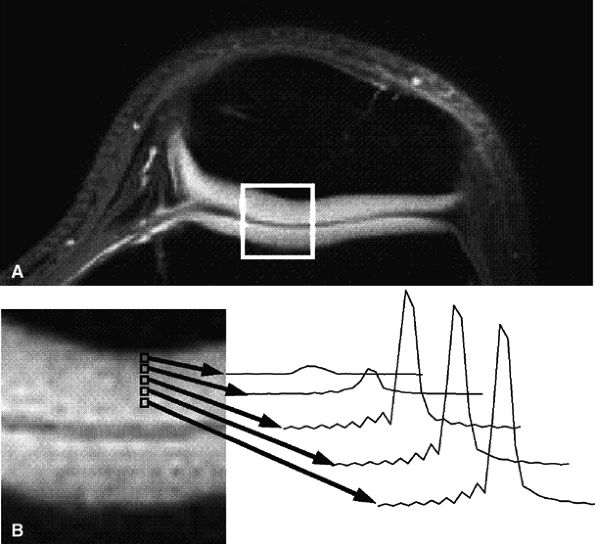

Short echo time projection reconstruction imaging of cartilage is a technique to detect ultrashort species in cartilage, potentially improving visualization of cartilage structure.47 Gold et al. described a method to obtain information from ultrashort echo time species in cartilage using projection-reconstruction spectroscopic imaging, disclosing spectra from voxels across the zones of articular cartilage that are reconstructed at the water frequency (Fig. 7.8).48 The latter technique also uses fat suppression to minimize chemical shift misregistration.

FIGURE 7.8 ● Axial MR images of the patellofemoral joint in a 25-year-old healthy volunteer using projection-reconstruction spectroscopic imaging sequence (TE = 200 μsec). (A) Water-frequency image. (B) Magnified image of articular cartilage from box in (A), along with spectra of the patellofemoral cartilage. Note the decreasing line width and increasing peak area as voxels progress from the cartilage–bone interface to the articular surface. (Reprinted by permission of

American Roentgen Ray Society, from Am J Roentgenol. 1998; 170:1223-1226.

) |